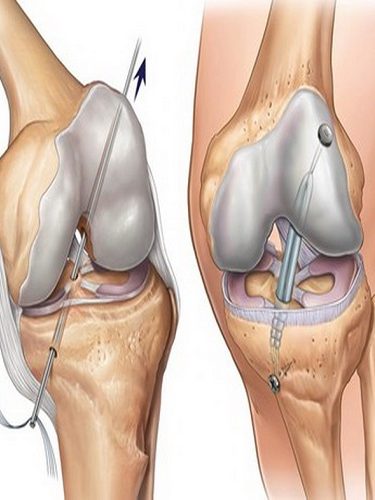

– OVER KİST AMELİYATI (YUMURTALIK KİSTİ AMELİYATI) (OVER KİSTEKTOMİ) Hemen her kadında hayatını belirli bir döneminde over kistlere rastlanabilmektedir. Bu kistlerin farklı tüpleri bulunmaktadır. Bu çeşitliliğe uygun tedavi yöntemleri de bulunmaktadır. Over kistlerinde en sık rastlanan şikayetler cinsel ilişki sırasında ağrı, kasık ağrısı, karında şişkinlik veya basınç hissi ve adet düzensizlikleridir. Yumurtalık (over) kistleri her…